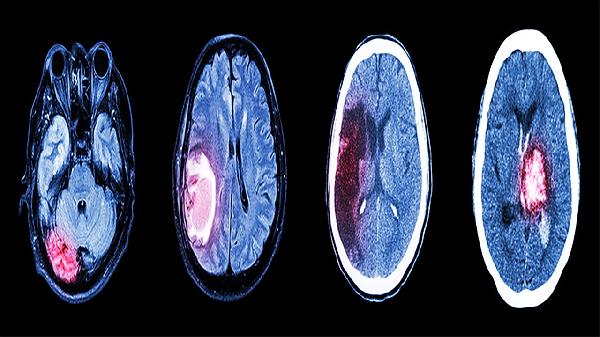

脑得生片通过活血化瘀作用改善中风患者的脑部血液循环,适用于缺血性中风急性期和恢复期。其成分中的三七、红花等能抑制血小板聚集,促进脑组织供血,缓解因瘀血阻滞导致的肢体功能障碍。使用时应配合抗血小板聚集药物如阿司匹林肠溶片,但需在医生指导下联合用药。

三、中风后遗症

针对中风后遗存的半身不遂或言语不利,脑得生片联合康复训练可促进神经功能重塑。药效学研究显示其中葛根素能减轻脑水肿,与胞磷胆碱钠胶囊同用时可加速神经修复。重度后遗症患者建议配合针灸治疗。